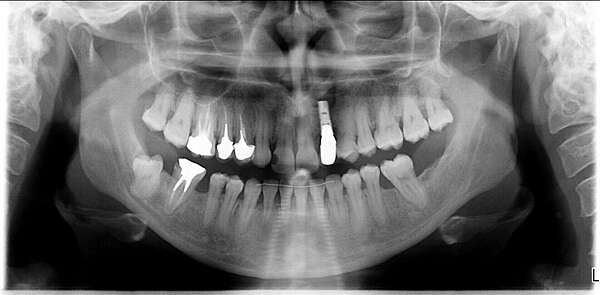

"Aménagement d'un espace pour remplacer une incisive latérale absente"